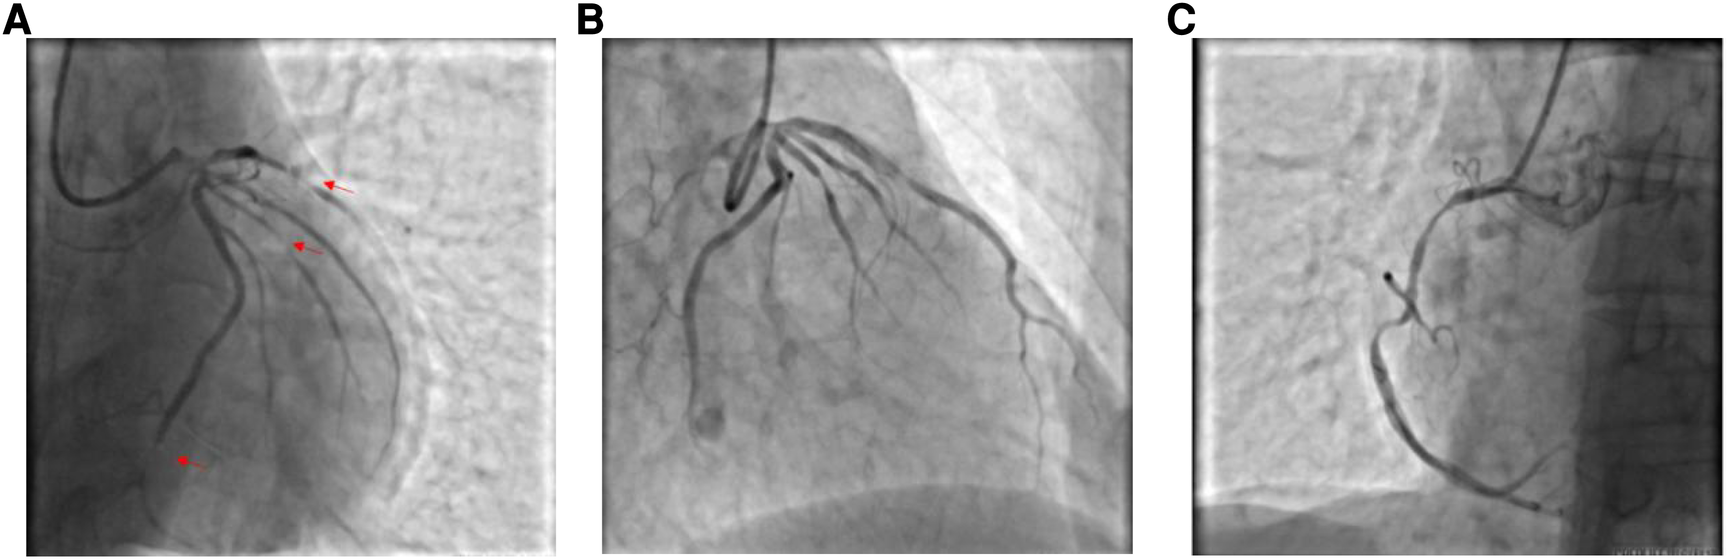

A 59-year-old male was admitted to our center, complaining of persistent chest pain over three days. He reported a 40-year history of heavy smoking and sporadic alcohol consumption for 18 years. His medical, allergy, and family histories were unremarkable. On admission, myocardial injury biomarkers revealed a myoglobin level of 45.4 ng/ml (0–121 ng/ml), a CK-MB mass of 4.85 ng/ml (0–3.38 ng/ml), and an ultrasensitive troponin I level of 2.47 ng/ml (0–0.034 ng/ml). The electrocardiogram (MAC800 model, GE Company) revealed an acute, extensive anterior wall myocardial infarction (Figure 1). Further, an echocardiogram (vividE9 model, GE Company) identified a left ventricular ejection fraction amounting to 56%, coupled with segmental motion abnormalities of the ventricular wall and a decreased amplitude of the lower ventricular septal pulsation. Following the diagnosis of “coronary artery atherosclerotic heart disease, extensive anterior myocardial infarction with Killip grade I classification”, a coronary angiogram was executed on the fifth day of the patient's hospital stay. Local stenosis of 95% within the proximal Left Anterior Descending artery (LAD) was evident, with a Thrombolysis in Myocardial Infarction (TIMI) flow grade of 3 (Figure 2A). Meanwhile, the Left Circumflex artery (LCX) showed non-significant stenosis, maintaining a TIMI grade of 3 (Figure 2B). Moreover, diffuse stenosis from the proximal to middle and distal segments of the Right Coronary Artery (RCA) was noted, along with greater than 90% stenosis, preserving a TIMI grade 3 flow (Figure 2C). We proposed to perform stenting for LAD, but the patient had a sudden onset of a peripheral red rash, decreased intracoronary pressure, and dyspnea during angiography. Re-evaluation angiography revealed proximal LAD occlusion, stenosis of the Obtuse Marginal artery (OM) and LCX, and diffuse RCA stenosis with distal segment occlusion (Figure 3A). The patient's blood pressure dropped to 55/35 mmHg, while his heart rate was 108 bpm. We attributed this to an allergic reaction and promptly administered adrenaline 0.1 mg, dexamethasone 10 mg, morphine injection 3 mg immediately, and norepinephrine infused to relieve the allergic reaction and maintain blood pressure. At the same time, continuous and large amounts of intracoronary nitroglycerin was given, after which the patient's symptoms gradually subsided, stenosis improved (Figure 3B), and RCA stenosis improved significantly after half a minute of nitroglycerin administration (Figure 3C). Following a mid-segment LAD stent implantation, blood flow was restored (Figure 4). Postoperatively, his heart rate was 103 bpm, his blood pressure was 107/63 mmHg, and he was transferred to the coronary care unit for further surveillance. Postoperative examination: the patient was clear and cooperative,but a generalized red rash remained. He was diagnosed with Type II Kounis Syndrome with cardiogenic shock induced by iodophorol. His management included promethazine, vitamin C, norepinephrine and dopamine, after which the patient's blood pressure was maintained at 100/60 mmHg. On the first postoperative day, his blood pressure was 106/63 mmHg, his pulse was 75 bpm, and his level of consciousness was normal. The red rash gradually faded. Laboratory studies exhibited a cardiac troponin I level of 0.582 ng/ml (0–0.034 ng/ml) and an elevated high-sensitivity C-reactive protein level of 87.52 mg/L (0–3.5 mg/L). His IgM level was normal at 0.55 g/L (0.3–2.2 g/L), and his IgE level was less than 18.80 IU/ml (<100 IU/ml). Four days after the surgical intervention, the patient reported no discomfort, and his ultrasensitive troponin I level was down to 0.159 ng/ml (0–0.034 ng/ml). He was discharged with instructions for regular antiplatelet medication and future caution with contrast agents.

Figure 2

(A) Coronary angiogram showing limited stenosis in the proximal segment of the LAD, up to 95% or more, with antegrade TIMI grade 3; (B) Coronary angiogram showing no significant stenosis in the LCX, with antegrade TIMI grade 3; and (C) Coronary angiogram showing diffuse stenosis from the proximal to the middle and distal segments of the RCA, up to 90% or more, with antegrade TIMI grade 3.